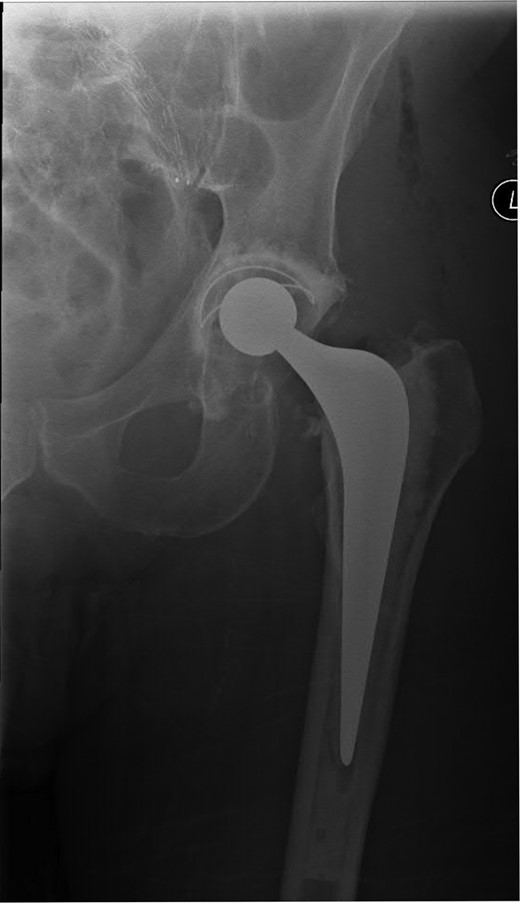

A 74-year-old male was admitted with an intracapsular fractured left neck of femur (Fig. 1). According to the NICE guidelines, he received a cemented THR (Fig. 2) via the posterior approach in the lateral decubitus position. Five weeks prior, he had an EVAR for a leaking AAA. Due to a calcified, narrow right common iliac artery (CIA), the EVAR consisted of a left aortouniiliac endograft with coil embolization of the right CIA and a femoro-femoral crossover graft (Figs 3 and 4).

Anteroposterior (AP) radiograph of the left hip demonstrating a complete and partially displaced, intracapsular fractured neck of femur.